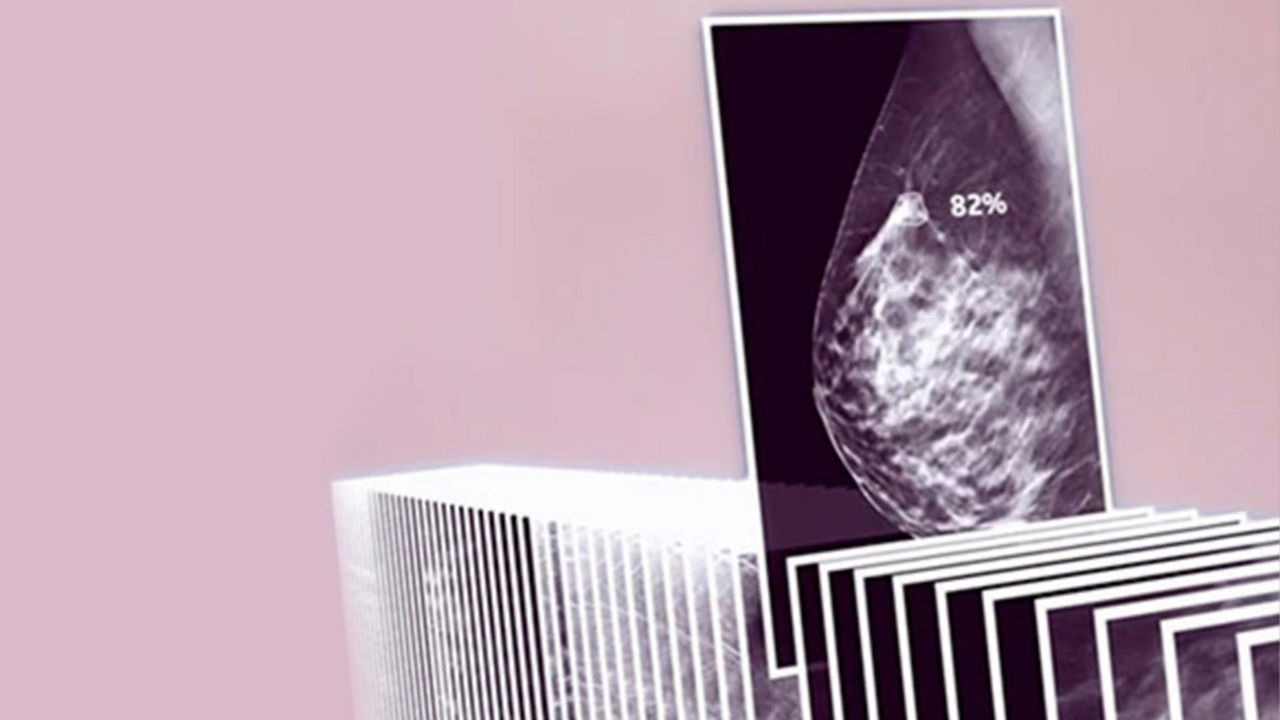

Leveraging transformational imaging technology to realize the promise of precision medicine and help deliver better outcomes. Our medical imaging products range from systems, including MRI, CT, PET, SPECT, Ultrasound, Mammography and X-ray, to digital and AI solutions to help drive healthcare digitialization, help enable faster exam workflow, improve clinical outcomes and increase efficiencies.